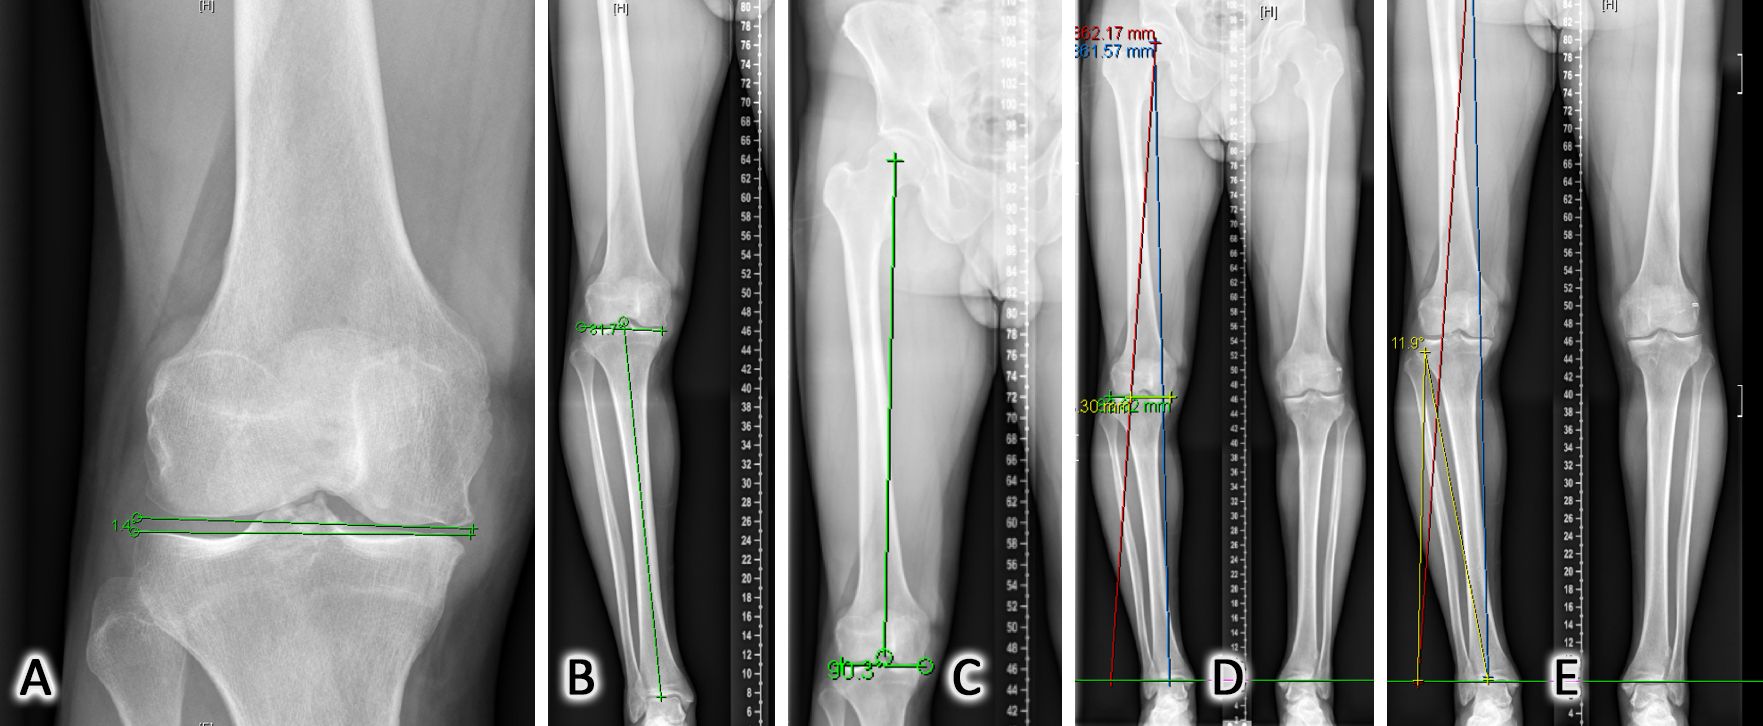

In the vast majority of cases knee osteotomy aims to correct an extra-articular deformity by shifting the mechanical axis from the overloaded femoro-tibial compartment to the contralateral side to unload cartilage and subchondral bone [12]. By correcting a pre-existing tibial or femoral metaphyseal abnormality the natural evolution of knee arthritis might be slowed down. The Hip-Knee-Ankle (HKA) angle is usually used to estimate the overall alignment of the lower limb. This angle represents the result of three components: the bony alignment of the femur and tibia as well as the intra-articular deformity resulting from articular surface wear at the concave and soft-tissue laxity on the convex side of the deformity. To allow proper planning of the bony correction the deformity analysis, introduced by D. Paley long time ago, is mandatory[13]. This includes the Lateral Distal Femoral Angle (LDFA), the Medial Proximal Tibia Angle (MPTA) as well as the Joint Line Convergence Angle (JLCA). The LDFA is defined by the angle between the femoral mechanical axis and the articular surface of the distal femur. The MPTA is defined by the angle between the tibial mechanical axis and the articular surface of the proximal tibia. The JLCA best reflects cartilage wear, meniscus loss and soft-tissue laxity of the contralateral side. (Figure 1 A-B-C)

Conventional planning

When dealing with a misaligned lower limb, the first step is to analyze if the deformity is located at the Tibia, Femur or both, which will influence where the osteotomy has to be performed. Not all varus knees have the deformity on the tibia only. 10-15% will need a femur or a combined femur and tibia osteotomy for correction, otherwise the jointline will be significantly malorientated. The next step is to decide for the proper postoperative frontal alignment and therefore to plan the desired correction. The planning must be performed on standardized full leg weight bearing X-rays [14]. Traditionally the new weight-bearing line should be within the “Fujisawa” point, which is 62% and 65% of the tibial plateau (with the medial side set at 0% and the outermost lateral aspect at 100%) [15]. Based on this point it is then possible to calculate the amount of correction needed in the frontal plane. One of the most common used technique for this correction angle α calculation is the Miniaci method [16] (Fig 1 D-E). Any existing soft tissue laxity on the concave side of the deformity (JLCA > 2 mm) has to be included in this bony correction angle calculation, otherwise the leg might be overcorrected.

The described conventional planning is focusing on the frontal plane only. PSCG includes the option of a much more sophisticated 3D planning procedure (Figure 1F).